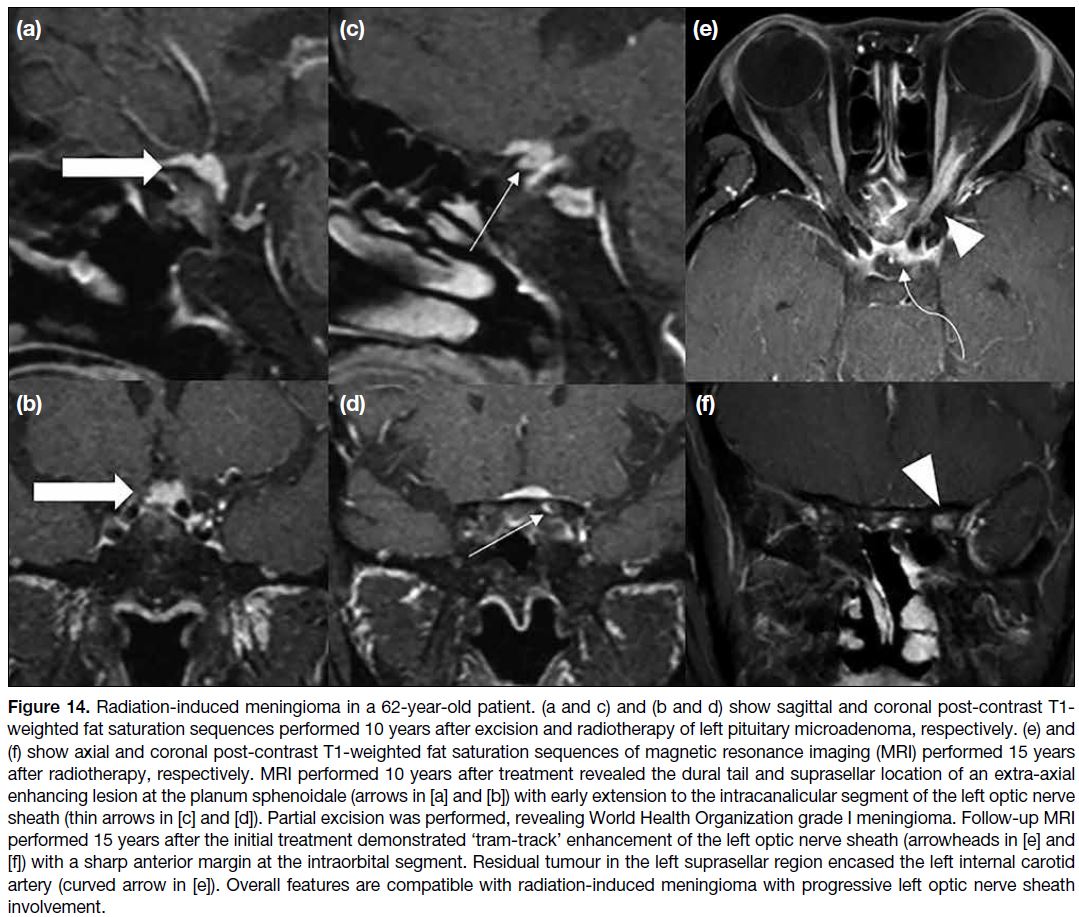

Figure 14. Radiation-induced meningioma in a 62-year-old patient. (a and c) and (b and d) show sagittal and coronal post-contrast T1-weighted fat saturation sequences performed 10 years after excision and radiotherapy of left pituitary microadenoma, respectively. (e) and

(f) show axial and coronal post-contrast T1-weighted fat saturation sequences of magnetic resonance imaging (MRI) performed 15 years after radiotherapy, respectively.

MRI performed 10 years after treatment revealed the dural tail and suprasellar location of an extra-axial enhancing lesion at the planum

sphenoidale (arrows in [a] and [b]) with early extension to the intracanalicular segment of the left optic nerve sheath (thin arrows in [c] and

[d]). Partial excision was performed, revealing World Health Organization grade I meningioma. Follow-up MRI performed 15 years after the

initial treatment demonstrated ‘tram-track’ enhancement of the left optic nerve sheath (arrowheads in [e] and [f]) with a sharp anterior margin

at the intraorbital segment. Residual tumour in the left suprasellar region encased the left internal carotid artery (curved arrow in [e]). Overall

features are compatible with radiation-induced meningioma with progressive left optic nerve sheath involvement.